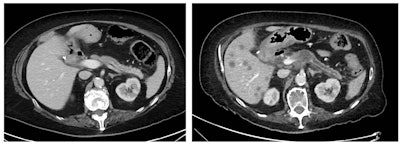

The tumor is not visible on either the precontrast scan or in the portal venous phase. It is only visible as a hypovascular mass on the later arterial phase. This technique is important when looking for pancreatic cancer. Courtesy of Dr. Alexandre Pérez Girbes, La Fe University and Polytechnic Hospital, Valencia, Spain.In CT, the dose concentration and rate of contrast administration are vitally important to identify pancreatic tumors, and the use of spectral CT or dual-energy CT scanners can help to pick up isoattenuating tumors at low or standard energy, he pointed out. For further reading in this area, Marti-Bonmati recommends the recent "Insights into Imaging" article by Dr. Hongwei Liang and colleagues.